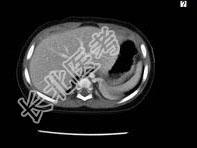

- 单项选择题男婴,11月, 咳嗽,结合图像, 最可能的诊断是 ( )

A、畸胎瘤

B、肺隔离症

C、肾母细胞瘤

D、嗜咯细胞瘤

E、神经源性肿瘤